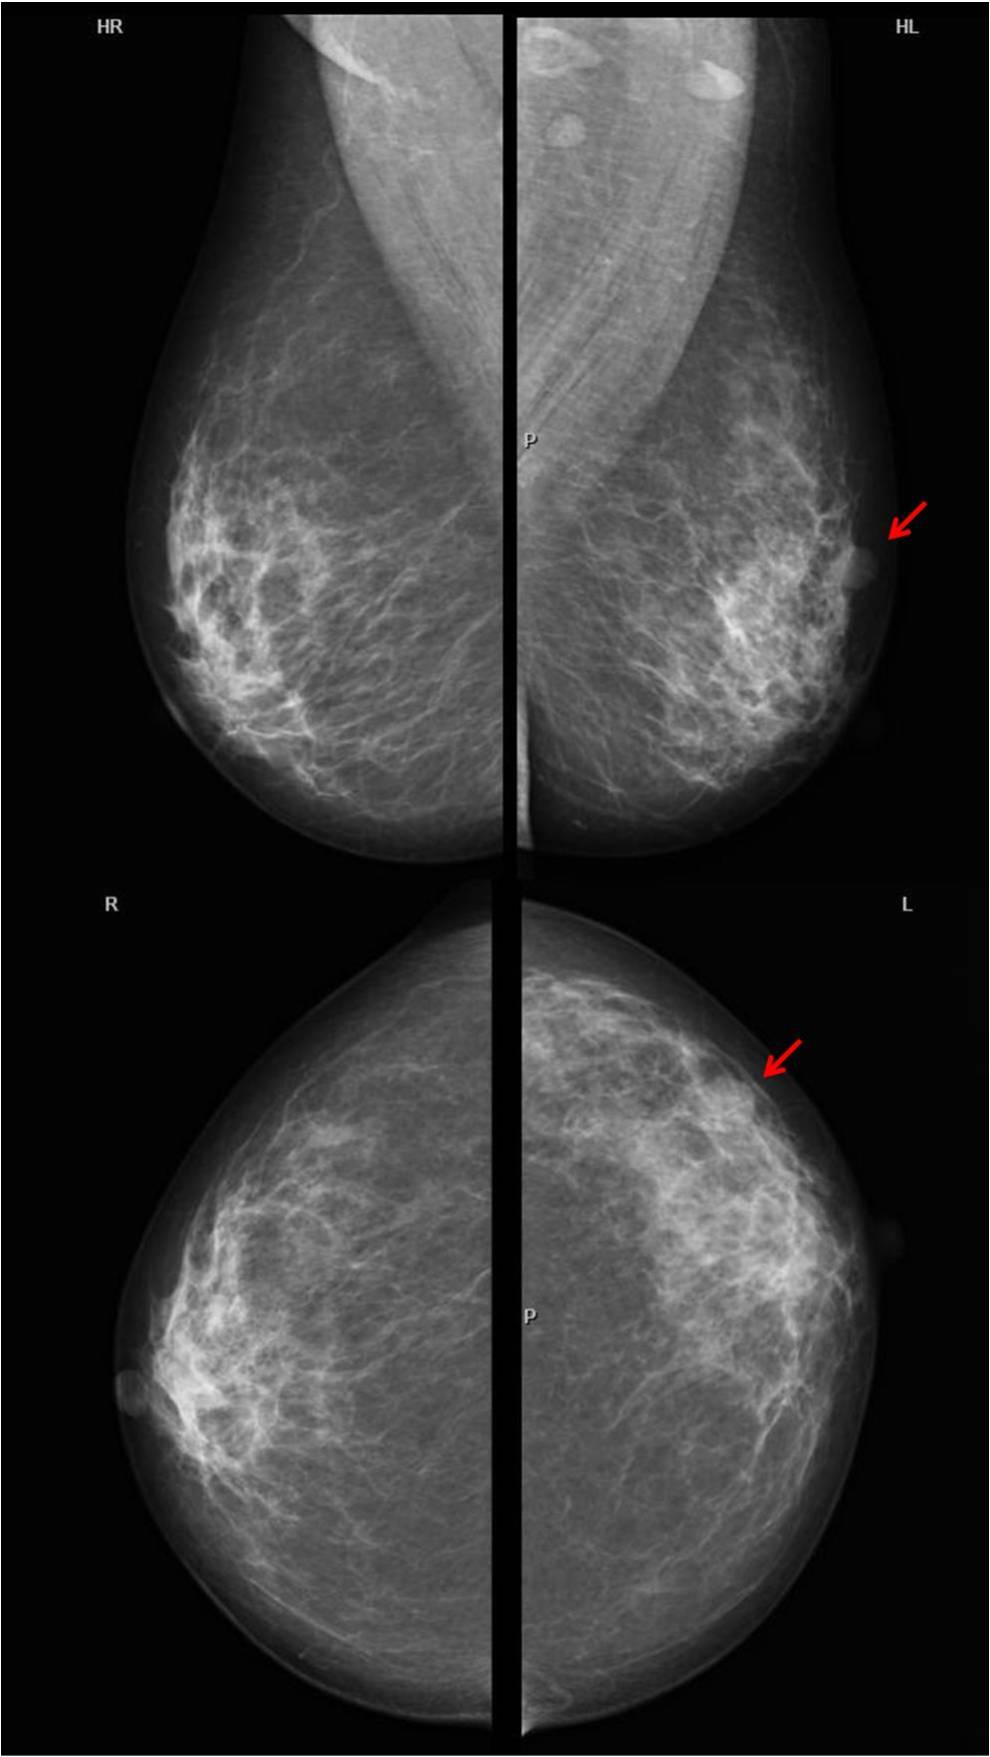

October 2020

A 49-year old asymptomatic female underwent routine screening mammogra...

Read More